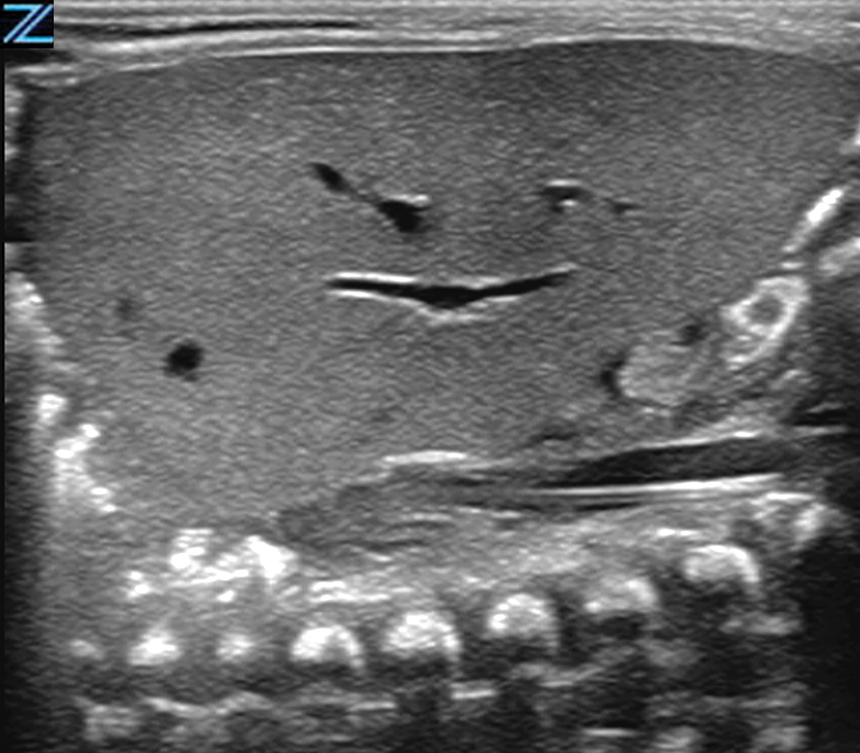

Intussusception B-Mode | L14-5w